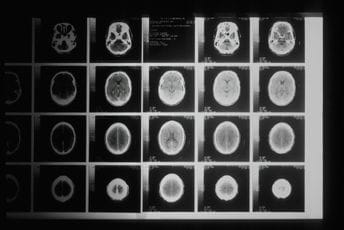

Nakon što su uporedili mozgove više od 3.800 ljudi starosti od nula do 90 godina koristeći MRI skeniranje koje mapira neuronske veze, naučnici su identifikovali četiri ključne prekretnice koje označavaju početak i kraj starenja mozga.